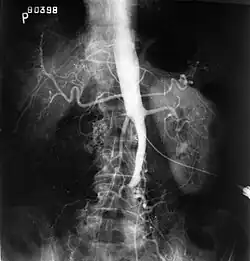

El síndrome de Leriche o enfermedad oclusiva aortoiliaca es una condición patológica que consiste en la oclusión ateroesclerótica que compromete la aorta abdominal y/o las arterias ilíacas comunes.

Tríada diagnóstica: pulsos femorales ausentes o disminuidos, claudicación o dolor al caminar en miembros inferiores (cadera y pantorrillas) y disfunción eréctil.

Bypass vascular o puente con injerto aortobifemoral es el tratamiento definitivo. La prevención secundaria se hace con la supresión total del tabaco. En caso de que se presente gangrena de una extremidad, se debe amputar.